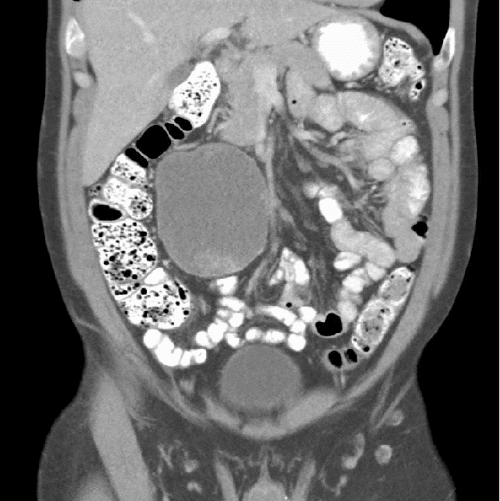

The patient is a 63-year-old male whose chief complaint was abdominal bloating for a couple of years. He denied any associated abdominal pain, nausea, vomiting, diarrhea, constipation, or any weight loss. His abdominal exam was significant for a palpable right upper quadrant mass. An abdominal ultrasound showed a right upper quadrant complex mass but no other abnormality. A follow-up CT confirmed a complex low-attenuation mass measuring 8.4 × 7.2 × 9.6 cm in the right abdomen abutting and compressing the head and the second and third portion of the duodenum, given the proximity of the mass to the duodenum and pancreas, pancreatic cancer was a suspected (Figure 1 and Figure 2). Therefore, an MRI and magnetic resonance cholangiopancreatography (MRCP) was done to evaluate and assess the anatomical delineation of the mass related to the pancreas and duodenum.

Figure 2. Coronal CT Showing Large Intra-Abdominal Epidermoid Cyst. Published with Permission

The laparoscopic technique provides an effective method of surgical management in cases of pancreatic and splenic cystic lesions, avoiding the shortcomings of open surgery.5 However, laparoscopy is limited to the size of the cysts and the location, which may render minimally invasive surgery a risky option. In our case, the mass was a complex low-attenuation mass measuring 8.4 × 7.2 × 9.6 cm in the right abdomen abutting and compressing the head of the pancreas and the second and third portion of the duodenum (Figure 1 and Figure 2). In this case, laparotomy was deemed the best option to ensure complete and safe resection. There is always a concern for local recurrence of the cysts; the management and treatment are based on symptoms if they recur. These cysts are often benign, so chemotherapy or radiation is not warranted. However, there have been reports of these cysts having malignant transformation into squamous cell cancer.6 In our case, the patient underwent resection with the official pathology from the excisional biopsy, indicating the mass to be an epidermoid cyst with no malignancy noted in the tissue. Postoperatively, the patient's initial presenting symptoms had resolved entirely without any signs of recurrence after twelve months.